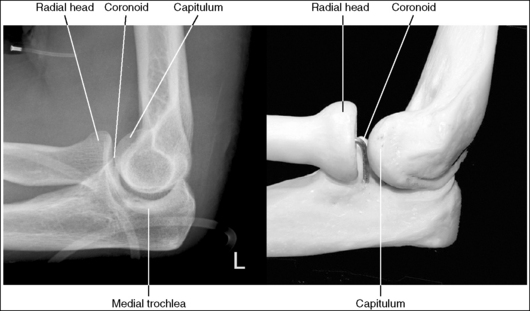

The elbow is in a lateral projection. The distal humerus demonstrates three concentric arcs, which are formed by the trochlear sulcus, capitulum, and medial trochlea. The elbow joint space is open, and the radial head is superimposed over the coronoid process.

• A lateral elbow projection is obtained when the humeral epicondyles are positioned directly on top of each other, placing an imaginary line drawn between them perpendicular to the IR. To obtain this humeral epicondyle positioning, place the humerus parallel with the IR and elevate the distal forearm until the palpable medial and lateral epicondyles are superimposed (Figure 4-78). This positioning aligns the trochlear sulcus, capitulum, and medial trochlea into three concentric (having the same center) arcs (Figure 4-79). The trochlear sulcus is the small center arc. It moves very little when a positional change is made and works like a pivoting point between the capitulum and medial aspect of the trochlea. The largest of the arcs is the medial aspect of the trochlea. It is demonstrated very close to and slightly superimposed on the curve of the trochlear notch. The intermediate-sized arc is the capitulum. When these three arcs are in accurate alignment, the elbow joint is visualized as an open space and the anterior and proximal surfaces of the radial head and coronoid process are aligned.

Figure 4-79 AP (left) and lateral (right) images showing anatomy of the distal humerus. (From Martensen K III: The elbow, In-Service Reviews in Radiologic Technology, 14[11], 1992.)

• Importance of accurate positioning. The distal humerus, radial head, and coronoid process are misaligned when the proximal humerus and distal forearm are inaccurately positioned. Proximal humerus positioning determines the alignment of the distal surfaces of the capitulum and medial trochlea, whereas distal forearm positioning determines the AP alignment of the capitulum and medial trochlea. Proximal humerus and distal forearm positioning also determines the alignment of the radial head and coronoid process. Depression or elevation of the proximal humerus moves the radial head anteriorly or posteriorly on the coronoid process, respectively. Depression or elevation of the distal forearm shifts the radial head distally or proximally, respectively, to the coronoid process. To help understand how the distal humerus and radial head move together, remember that ligaments connect the capitulum and the radial head, so any movement in one causes an equal amount of movement in the other. Precise positioning is a must to obtain a true lateral elbow projection. It takes only a small amount of inaccurate positioning to misalign the distal humerus and close the elbow joint space.